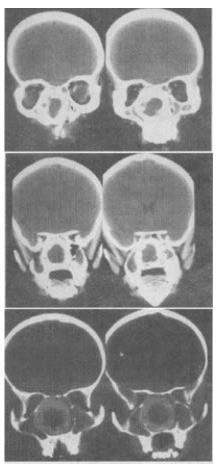

试题详情 单项选择题 女,14岁,渐进性鼻塞2年余,右眼肿数月,CT如图所示,最可能的诊断是()。A、筛骨骨肉瘤B、筛骨骨纤维结构不良C、筛骨软骨瘤D、筛骨结核E、筛骨骨化性纤维瘤正确答案:E答案解析:关注下方微信公众号,在线模考后查看 热门试题 位于第三脑室顶的结构是:()直肠癌根治术后复查的最佳方法是:()肾上腺转移瘤,最常见的原发肿瘤是()。颞下窝的后界是:()在CT轴位图像上视神经直径一般为:()基底节不包括:() 最新试题 急性硬膜下血肿的不典型CT表现为:()下列关于“膀胱结核”的说法,错误的是()。脑膜膨出或脑膜脑膨出易发生在哪个部位:()鞍上池前外侧与下列哪个结构相连:() 患者女,51岁,心脏手术后,突感胸痛,结合CT图像,最可能的诊断左支气管动脉常起源于下列哪个动脉:()